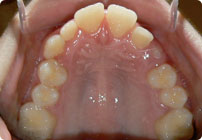

Femenino

Antes

Despues

Caso: 19 años

Adulto: Clase III

Mordida Abierta Anterior

Mordida Cruzada Anterior y Posterior

Endo necesitado para #19

Extract U5’s, LR4, LL6

6 alambres superiores

5 alambres inferiores

Elásticos Clase III 2oz. TP Verde

Retenedores: Interior Fijo de TMA y Hawley en superior

Tiempo de tratamiento: 21 Visitas